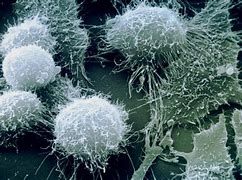

1985年,美国加利福尼亚大学伯克利分校的玛丽安·C·戴蒙德(Marian C. Diamond)从哈维那里要到了4个脑块,她对研究爱因斯坦的脑胶质细胞非常感兴趣,胶质细胞对神经元起支持作用。在前期的小鼠试验中,戴蒙德发现,相比无刺激的环境,暴露在感官刺激比较多的环境中,会使胶质细胞与神经元的数量比升高。她猜测,或许有较高比例的胶质细胞,分布于爱因斯坦某些区域的大脑皮层中,这些脑区与较高级的神经功能例如想象、记忆力及注意力有关联。

当戴蒙德检查哈维给她的4个脑块时,她在其中一个脑块中发现了她正在研究的现象,并断定,这个脑块中的神经胶质细胞的比例之所以比较高,是因为爱因斯坦对这部分组织的使用频度比较高。这一发现受到了媒体的狂热追捧,但是,记者们的报道让人们产生了这样的印象:因为胶质细胞较多,所以爱因斯坦很会思考,而不是因为爱因斯坦常常进行思考,所以胶质细胞较多。

此后不久,科学家试图从解剖学的角度对爱因斯坦的超凡智力做出解释。20世纪90年代,美国亚拉巴马大学伯明翰分校的布里特·安德森(Britt Anderson)和加拿大麦克马斯特大学的心理学家桑德拉·维特尔森(Sandra Witelson)将爱因斯坦的天资归功于他脑组织的其他特性。安德森注意到,爱因斯坦大脑前额叶区的脑细胞密度高于常人。而维特尔森则发现,爱因斯坦的顶盖异常缺失,而顶盖是缝隙结构的一部分,能把大脑顶叶分为不同区域。据此,维特尔森声称,爱因斯坦拥有一个扩大了的皮层区域,这个区域与视觉空间及数学能力有关。

在接下来的10年中,科学家又对职业音乐家和伦敦出租车司机的异常脑部结构做了很多有趣的研究,但并没有关于爱因斯坦脑组织的报道。直到2007年,哈维去世前后,现名为罗格斯·罗伯特·伍德·约翰逊医学院(Rutgers Robert Wood Johnson Medical School)的神经眼科医生弗雷德里克·E·莱波雷(Frederick E. Lepore)发现了一些未曾曝光的爱因斯坦脑部照片,他将这些照片分享给了美国佛罗里达州立大学的古人类学家迪安·福尔克(Dean Falk),后者主要从事脑演化研究。福尔克发现,爱因斯坦的脑部形态有一些不同寻常的特点,比如大脑皮层上有个球状突起物,形如“Ω”,前期研究认为,这一特征与音乐天赋有关。“我们可以进行有意思的推断,”福尔克写道,“爱因斯坦天赋异禀,在某种程度上或许与他的大脑皮层的解剖结构异于常人有关。”

关于爱因斯坦脑部的最新研究,是福尔克与上海华东师范大学的门卫伟(Weiwei Men)于2013年在线发表的一项研究,他们为这位物理学家惊人的思维能力,找到了另一个解剖学上的解释——除了独特的皮层形态和细胞结构外,福尔克与门卫伟认为,“至少在爱因斯坦大脑的两个半球之间,有某些区域的交流通路有所增强”。他们是通过比较爱因斯坦本人和对照人群的胼胝体(连接左右大脑的神经纤维束)的横截面积来进行推断的。